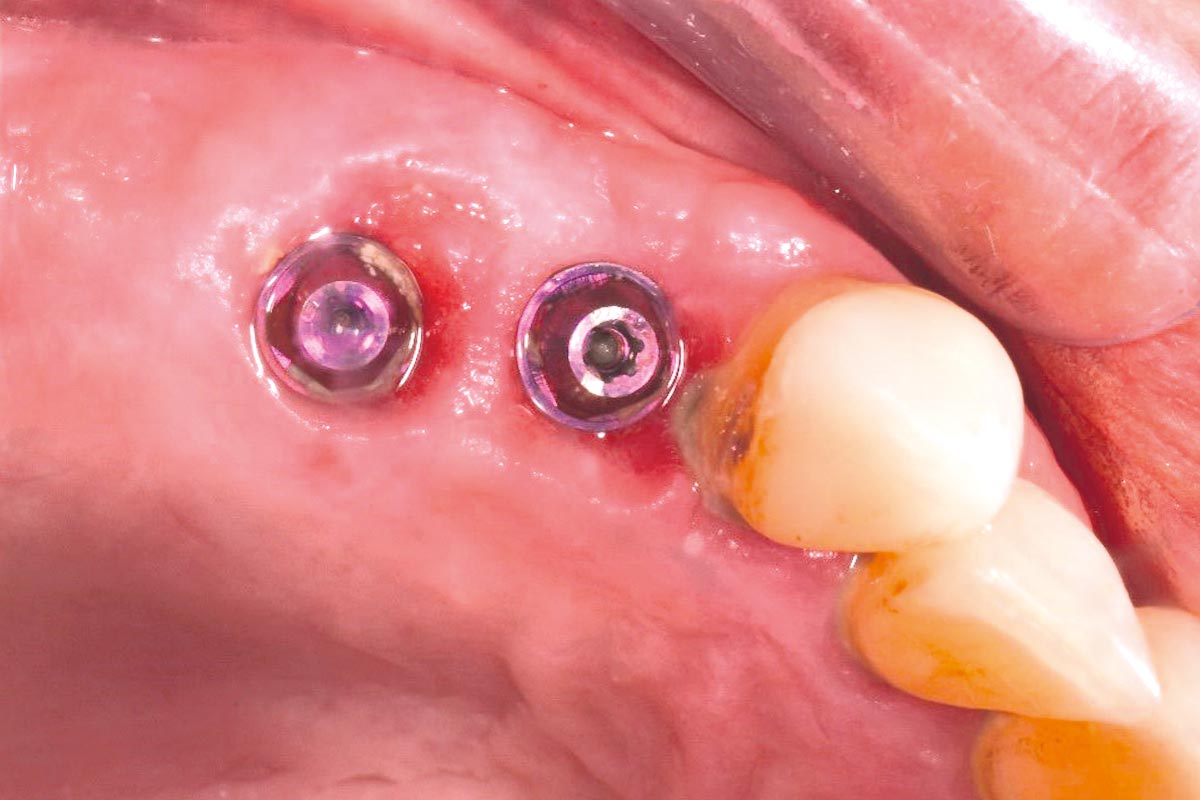

At the six-month re-entry, insufficient regeneration of the buccal plate was observed, compromising the available bone volume for implant placement. To address this deficiency, NOVAMag® SHIELD was introduced to reconstruct the buccal plate. Thus, an implant was placed followed by a membrane placement between the periosteum and the remaining buccal bone without fixation. Additional bone augmentation was performed to facilitate guided bone regeneration.